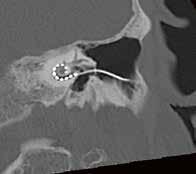

Die HNO-Klinik der Medizinischen Hochschule Hannover setzt ca. 500 Cochlea-Implantate ein, womit sie aktuell weltweit den Spitzenreiter darstellt. Für die OP-Planung ist eine sehr gute örtliche Auflösung und ein starker Kontrast des Felsenbeins erforderlich, um dem Operateur, der die Elektrode in die Schnecke das Runde Fenster zielgenau einführen muss, eine gute Planungsgrundlage zu schaffen. Auch muss post die intracochleare Lage kon werden, was technisch eine große Herausforderung darstellt, da die Strukturen in diesem Areal sehr fein sind und durch das implantierte Metall Aufhärtungsartefakte ent die Diagnostik dadurch erschweren.

Goldstandard war bis dato das DVT, das durch die Cone Beam Technik stark reduzierte Aufhärtungsartefakte aufwies und somit genaue Aussagen zwecks Lagekontrolle liefern konnte. Es kommt jedoch für einen Großteil der Patienten (Kinder 1–5) aufgrund der vorher erwähnten Gründe nicht in Frage. Ein großer Vorteil des neuen Canon CTs ist die bereits gut etablierte Metallartefakt-Reduktion SEMAR,die durch Algorithmen die Artefakte stark reduzieren kann. Es entsteht dadurch

keine wesentliche Einschränkung zur Identifizierung der ersten Kontaktelektrode im Vergleich zum DVT.

Auch der neuentwickelte Deep Learning Algorithmus AiCE des Canon Aquilion ermöglicht die Reduktion der Dosis, bei gleichbleibendem bzw. verbessertem Bildeindruck. AiCE bietet zudem eine scharfe Abgrenzung feiner Strukturen und reduziert das durch Low-DoseTechnik auftretende Rauschen. //

2. Vergleich eines cranialen CTs mit und ohne Deep Learning Rekonstruktion AiCE:

CTDI

30,2 mGy 544,6 mGy*cm

Felsenbein-CT Felsenbein CT-Rekonstruktion

Elektrode

CCT AIDR

der

Felsenbein-DVT

CCT AiCE

Vergleich

DVT: CDTI DLP Volumen-CT 6,5 mGy 39 mGy*cm DVT 7,3 mGy 76,6 mGy*cm Vorgänger-CT 17,1 mGy 176 mGy*cm CT vs. DVT

„AiCE unterstützt die Diagnosefindung in der Neuroradiologie dank der sofort sichtbar besseren Bildqualität bei gleicher Dosis.“